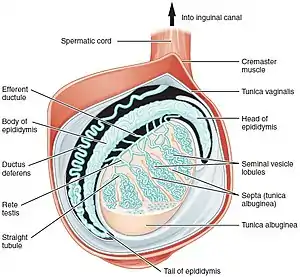

The major reproductive organs of the male can be grouped into three categories. The first category produces and stores sperm (spermatozoa). These are produced in the testicles, which are housed in the temperature-regulating scrotum; immature sperm then travel to the epididymis for development and storage. The second category are the ejaculatory fluid producing glands which include the Cowper's gland (also called bulbourethral gland), seminal vesicles, prostate, and vas deferens. The final category are those used for copulation and deposition of the sperm within the female; these include the penis, urethra, and vas deferens.

In males, this process is known as spermatogenesis, and takes place only after puberty in the seminiferous tubules of the testes. The immature spermatozoa or sperm are then sent to the epididymis, where they gain a tail, enabling motility. Each of the original diploid germ cells or primary spermatocytes forms four functional gametes which is each forever young. The production and survival of sperms require a temperature below the normal core body temperature. Since the scrotum, where the testes is present, is situated outside the body cavity, it provides a temperature about 3 °C below normal body temperature.